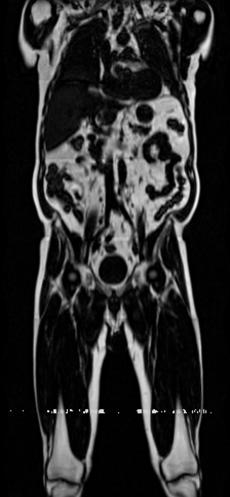

Magnetic Resonance Imaging (MRI) is a crucial diagnostic tool, but high-resolution scans are often slow and expensive due to extensive data acquisition requirements. Traditional MRI reconstruction methods aim to expedite this process by filling in missing frequency components in the K-space, performing 3D-to-3D reconstructions that demand full 3D scans. In contrast, we introduce X-Diffusion, a novel cross-sectional diffusion model that reconstructs detailed 3D MRI volumes from extremely sparse spatial-domain inputs—achieving 2D-to-3D reconstruction from as little as a single 2D MRI slice or few slices. A key aspect of X-Diffusion is that it models MRI data as holistic 3D volumes during the cross-sectional training and inference, unlike previous learning approaches that treat MRI scans as collections of 2D slices in standard planes (coronal, axial, sagittal). We evaluated X-Diffusion on brain tumor MRIs from the BRATS dataset and full-body MRIs from the UK Biobank dataset. Our results demonstrate that X-Diffusion not only surpasses state-of-the-art methods in quantitative accuracy (PSNR) on unseen data but also preserves critical anatomical features such as tumor profiles, spine curvature, and brain volume. Remarkably, the model generalizes beyond the training domain, successfully reconstructing knee MRIs despite being trained exclusively on brain data. Medical expert evaluations further confirm the clinical relevance and fidelity of the generated images.To our knowledge, X-Diffusion is the first method capable of producing detailed 3D MRIs from highly limited 2D input data, potentially accelerating MRI acquisition and reducing associated costs. The code is available on the project website https://emmanuelleb985.github.io/XDiffusion/.

Contributions: (i) We introduce X-Diffusion, a cross-sectional diffusion model that generates MRI volumes conditioned on a single input MRI slice or multiple slices. The proposed X-Diffusion achieves state-of-the-art results on MRI reconstruction and super-resolution compared to recent methods on BRATS, a large public dataset of annotated MRIs for brain tumors, and full-body MRIs from the UK Biobank dataset. (ii) We validate the generated MRIs on a wide range of tasks to ensure that they retain important features of the original MRIs (e.g., tumor profiles and spine curvature) without using this meta-information in the generation process. (iii) We showcase the generalization of trained X-Diffusion beyond the training domain (e.g., on knee MRIs not seen in training). (iv) We evaluated the generated brain and knee MRIs with medical experts (a surgeon and an oncologist) who anonymously could not distinguish the real from the generated MRIs in controlled experiments which provides a proof of concept for the potential clinical usefulness of the generated MRIs.

We conducted our experiments on two primary datasets for evaluations (BRATS & UK BioBank) and on two secondary datasets for out-of-domain generalization (IXI & fast knee MRI). BRATS is the largest public dataset of brain tumours consisting of 5,880 MRI scans from 1,470 brain diffuse glioma patients, and corresponding annotations of tumours [3, 42, 4]. All scans were skull-stripped and resampled to 1 mm isotropic resolution. All images have a resolution of 240 240 155, and we use the flair T2 sequence. Tumours are annotated for 3 classes: Whole Tumour (WT), Tumour Core (TC), and Enhanced Tumour Core (ET). UK Biobank is a more comprehensive dataset of 48,384 full-body MRIs from more than 500,000 volunteers[67], capturing diverse physiological attributes across a broad demographic spectrum. IXI is a dataset of T1-weighted 1.5 Tesla brain MRI images of 582 healthy subjects, freely available online [1]. Knee fastMRI is a public dataset of raw k-space data from NYU Langone[33, 80]. We use the test set provided (n=109) of fastMRI single coil, dimensions 640x372x30. These are center-cropped to 320x320x30.

Our results unequivocally highlight the superior performance of X-Diffusion in terms of both qualitative and quantitative metrics. Representative MRI volumes generated by our pipeline, when juxtaposed with ground-truth images, showcased remarkable similarity, with even intricate physiological features like tumor information, spine curvature, and fat distribution being accurately captured.

Notably, X-Diffusion achieves sota dB for a few input slices while baselines require more than 60 input slices to achieve similar performance (Figure 7). The margin is more than 12 dB PSNR for the 1-slice input in both the BRATS and the UK Biobank benchmarks (see Table 1 and Figure 6). For reference, two randomly sampled MRIs from the UK Biobank would have a PSNR of 15.95 dB 0.36 (on 4800 randomly sampled examples). The slices from 3D reconstructed volumes at varying depths and axis of rotation visually match the ground truths (see Figures 5 and Figure 4). We also plot the error map (Figure 4) of such X-Diffusion generations to highlight the differences with the ground truth MRIs.

Preservation of Spine Curvature. For the spine segmentation on UK Biobank, we use a UNet++ model [81] with Dice Loss and use the curvature prediction of the spine followed in [9]). We measure the Pearson correlation factor [9] of spine curvature measured on the generated MRIs where the input is a single MRI coronal slice, or a single sagittal slice against the curvature of reference real MRIs of the same samples. The correlation coefficients are 0.89 for the coronal MRIs and 0.88 for the sagittal MRIs on the test set of 308 human-annotated angles.